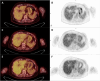

Gastric Metastases From Invasive Breast Lobular Carcinoma, Identified by [18F]FDG PET/CT, 20 Years After Primary Diagnosis: A Case Report

Invasive lobular carcinoma (ILC) of the breast is a rare subtype of breast cancer with distinct metastatic patterns. Although gastrointestinal metastases are rare, they can occur years after initial treatment. This case highlights the diagnostic challenges and management of late-onset gastric metastases. A 68-year-old woman with a history of ILC treated 20 years earlier presented with elevated tumor markers. [18F]fluorodeoxyglucose positron emission tomography/computed tomography (FDG PET/CT) revealed hypermetabolic lesions in the stomach and esophagus in this patient with previously diagnosed gastritis and gastroesophageal reflux disease. Endoscopy and biopsies confirmed the presence of metastatic ILC in the stomach. Adjustment of treatment, including exemestane and everolimus, followed by paclitaxel and tamoxifen, resulted in partial disease control. Late-onset gastrointestinal metastases of ILC are uncommon and require special vigilance, particularly in patients with associated benign gastrointestinal pathologies, which may delay diagnosis. Persistent or new-onset gastrointestinal symptoms in breast cancer patients warrant thorough evaluation, including FDG PET/CT imaging and histological confirmation.